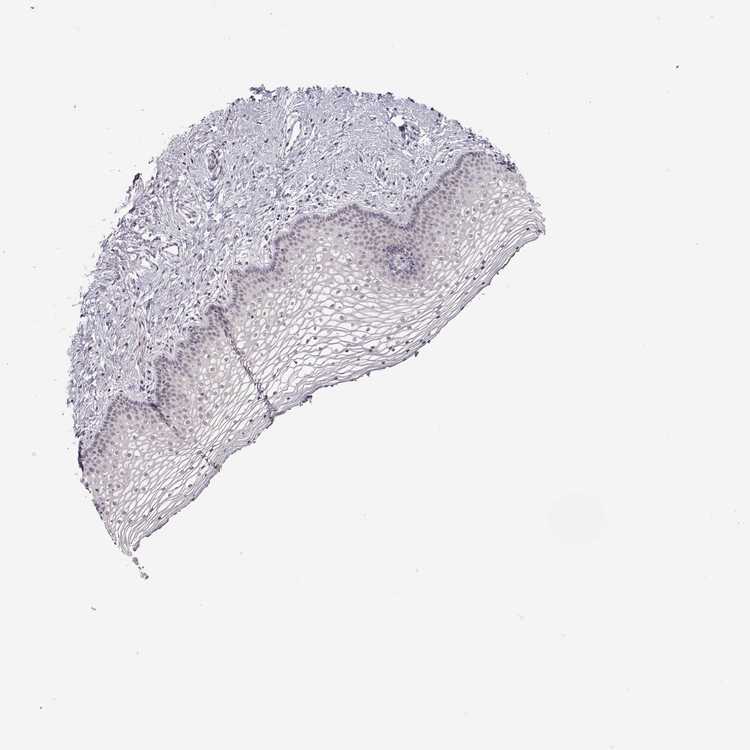

TISSUE PRIMARY DATA VAGINA Show tissue menu

VAGINA - Antibody stainingi

Antibody staining in the annotated cell types in the current human tissue is reported as not detected, low, medium, or high, based on conventional immunohistochemistry profiling in selected tissues. This score is based on the combination of the staining intensity and fraction of stained cells.

Each image is clickable and will lead to virtual microscopy that enables deeper exploration of all samples and also displays staining intensity scores, fraction scores and subcellular localization as well as patient and tissue information for each sample.

Antibody CAB020785

Squamous epithelial cells Not detected